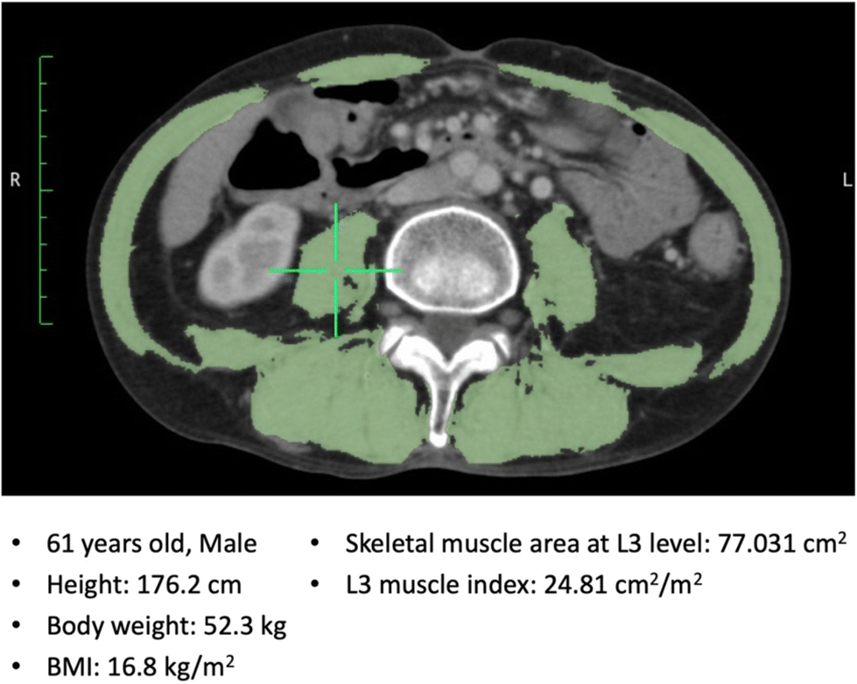

2. Muscle Mass Assessment at L3 Vertebra (CT scan)

What is measured: (Ref 2)

- Cross-sectional area (CSA) of skeletal muscles at the third lumbar vertebra (L3)

- Muscles included: psoas, erector spinae, quadratus lumborum, abdominal wall muscles

Why L3:

- Muscle area at L3 correlates strongly with whole-body muscle mass

Normal / Cut-off Values

| Sex | Skeletal Muscle Index (SMI) at L3 SMI = muscle CSA at L3 / height² |

| Male | ≥ 52.4 cm²/m² |

| Female | ≥ 38.5 cm²/m² |

Interpretation:

- Below cut-off → sarcopenia

Utility of L3-CT

- L3 CT gives precise, reproducible muscle mass assessment

- Often used in oncology, geriatrics, ICU patients

- Advantage: can use routine abdominal CT scans without extra radiation

Representative image of the skeletal muscle area at the L3 level. The skeletal muscle area was 77.031 cm² and L3 muscle index was 24.81 cm²/m². BMI body mass index, L3 the third lumbar vertebra. (Adapted from Ref 3)